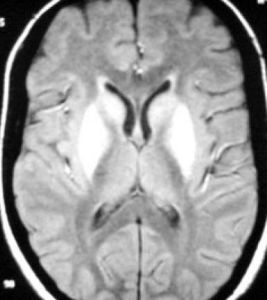

(3)掌握輸液速度和液量:對有肺水腫或腦水腫的病人應嚴格掌握輸液速度和液量。

(5)腎上腺皮質激素:重度中毒的病人可給腎上腺皮質激素,以抑制抗體對藥物的反應,改善腦水腫和肺水腫,解除支氣管痙攣及喉水腫。

(2)急性呼衰:由於菸鹼樣作用的結果,導致呼吸麻痹以至呼吸衰竭,主要是通氣障礙,血氣顯示PaO2<8.00kPa(60mmHg),PaCO2>6.0kPa(45mmHg)還可因支氣管分泌增加,肺水腫導致ARDS可見進行性吸氣性呼吸困難伴低氧血症,此時應早給氧、氣管插管,或氣管切開和機械通氣,可用呼氣末正壓(PEEP)或高頻通氣,同時給予地塞米松4~8mg靜脈推入,繼之靜脈點滴,每4~6小時1次,連用3天左右。

(6)反跳及有機磷溶劑的毒性作用:以樂果中毒最常見,即在搶救成功後3~10天又突然表現急性中毒症狀神志改變肺水腫以及呼吸衰竭。有的表現心律失常,病人可很快死亡。預防反跳的發生首先應徹底洗胃,阿托品解毒劑量應足夠,持續時間應較長。